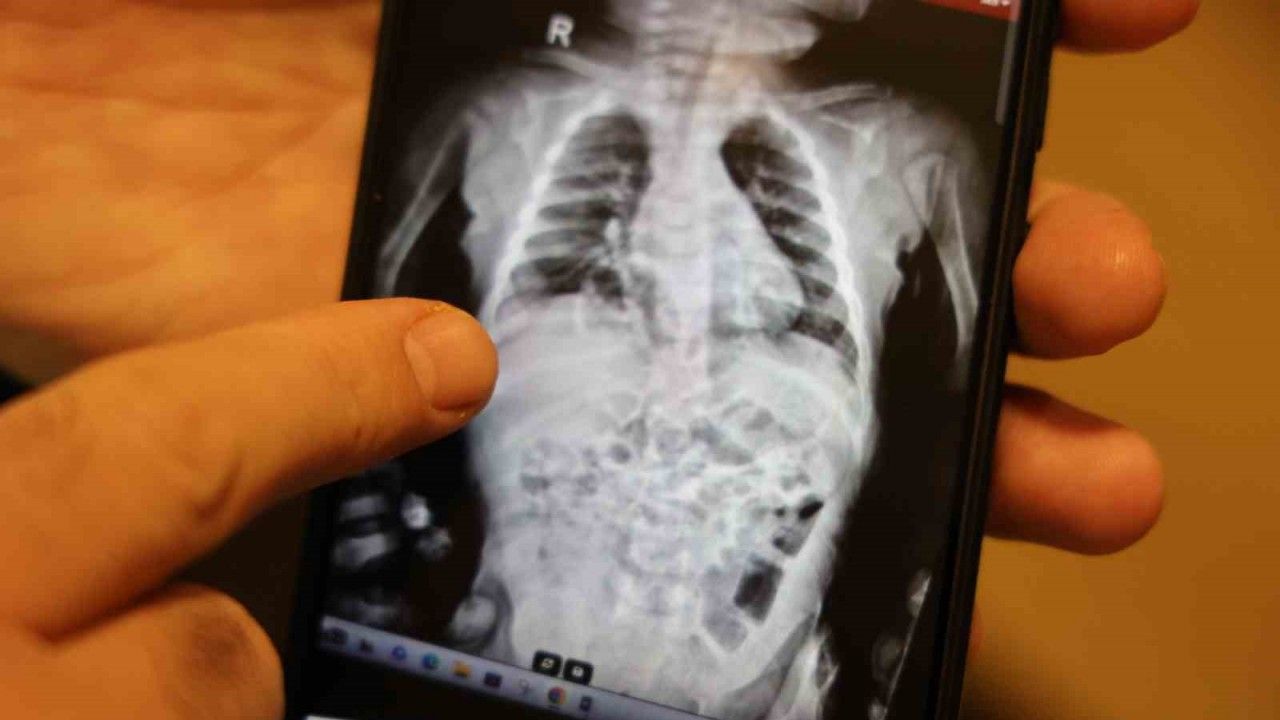

Op. Dr. Taner Kamacı, hastanın diyafram hernesi dedikleri bir rahatsızlıkla kendilerine başvurulduğu söyledi. Hastanın sık sık akciğer enfeksiyonu geçirip ve zatürre nedeniyle tedavi gören bir hasta olduğunu belirten Kamacı, bunları araştırırken çocuğun diyaframında doğuştan gelen bir yırtık olduğu ve bu yırtıktan bağırsaklarının karın içinde olması gerekirken göğüs boşluğuna doğru çıktığı ve akciğeri sıkıştırdığını tespit ettiklerini ifade etti. Kamacı, doğuştan itibaren böyle diyafram yırtıkları olduğuna değinerek, "Bu hastamızın özelliği diyafram fıtıklarının en nadir görülen tipi. Morgagni hernisi dediğimiz özel bir tip. Yaklaşık 200 bin doğumda bir görünen nadir vaka. Türkiye’de geçen sene 937 bin bebek doğmuş. Düşünün bu şekilde Türkiye’de sadece 5 hasta doğuyor bir yıl içinde. Akciğer filmleri ve tomografisiyle teşhisini koyduk" dedi.

Kapalı laparoskopik yöntemle ameliyatı yaptıklarını kaydeden Kamacı, "Ameliyatta göğüs boşluğuna çıkan bağırsakları karnın içine geri indirdik. Diyaframda olan yırtığı ya da fıtık kısmını dikerek kapalı yöntemle kapatıyoruz. Yaklaşık 1 saat süren bir ameliyatla hastamızı tedavi ettik. Bir sonraki gün de hastamızı taburcu ederek evine gönderdik. Bugün hastamızın kontrolünü yapıyoruz. Kontrolünde de her şey yolunda görünüyor. Fıtığında her hangi bir sıkıntı yok. Bundan sonra akciğer enfeksiyonu geçirmeden tamamen normal hayatına dönecek" şeklinde konuştu.